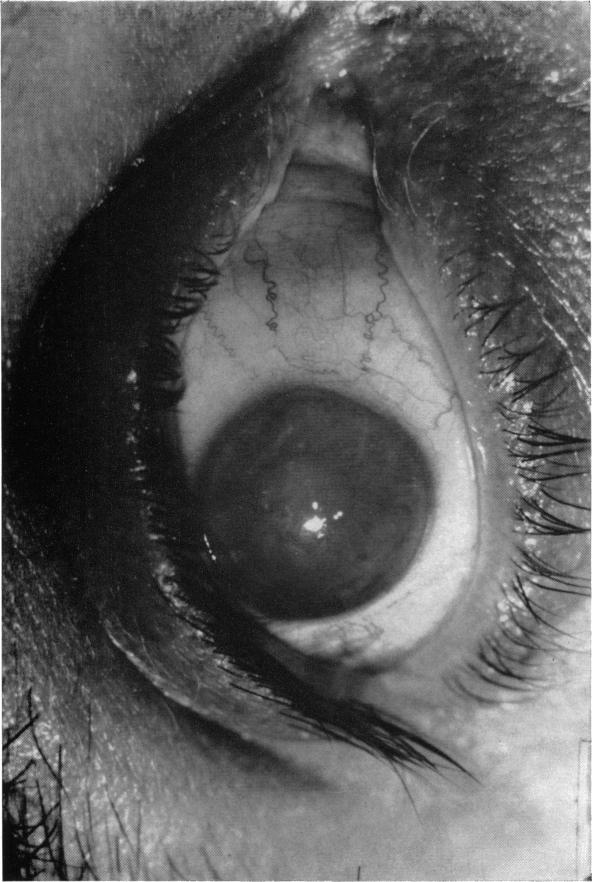

Hereditary deep dystrophy of the cornea (polymorphous).

Trans Am Ophthalmol Soc. 1969;67:235-64.